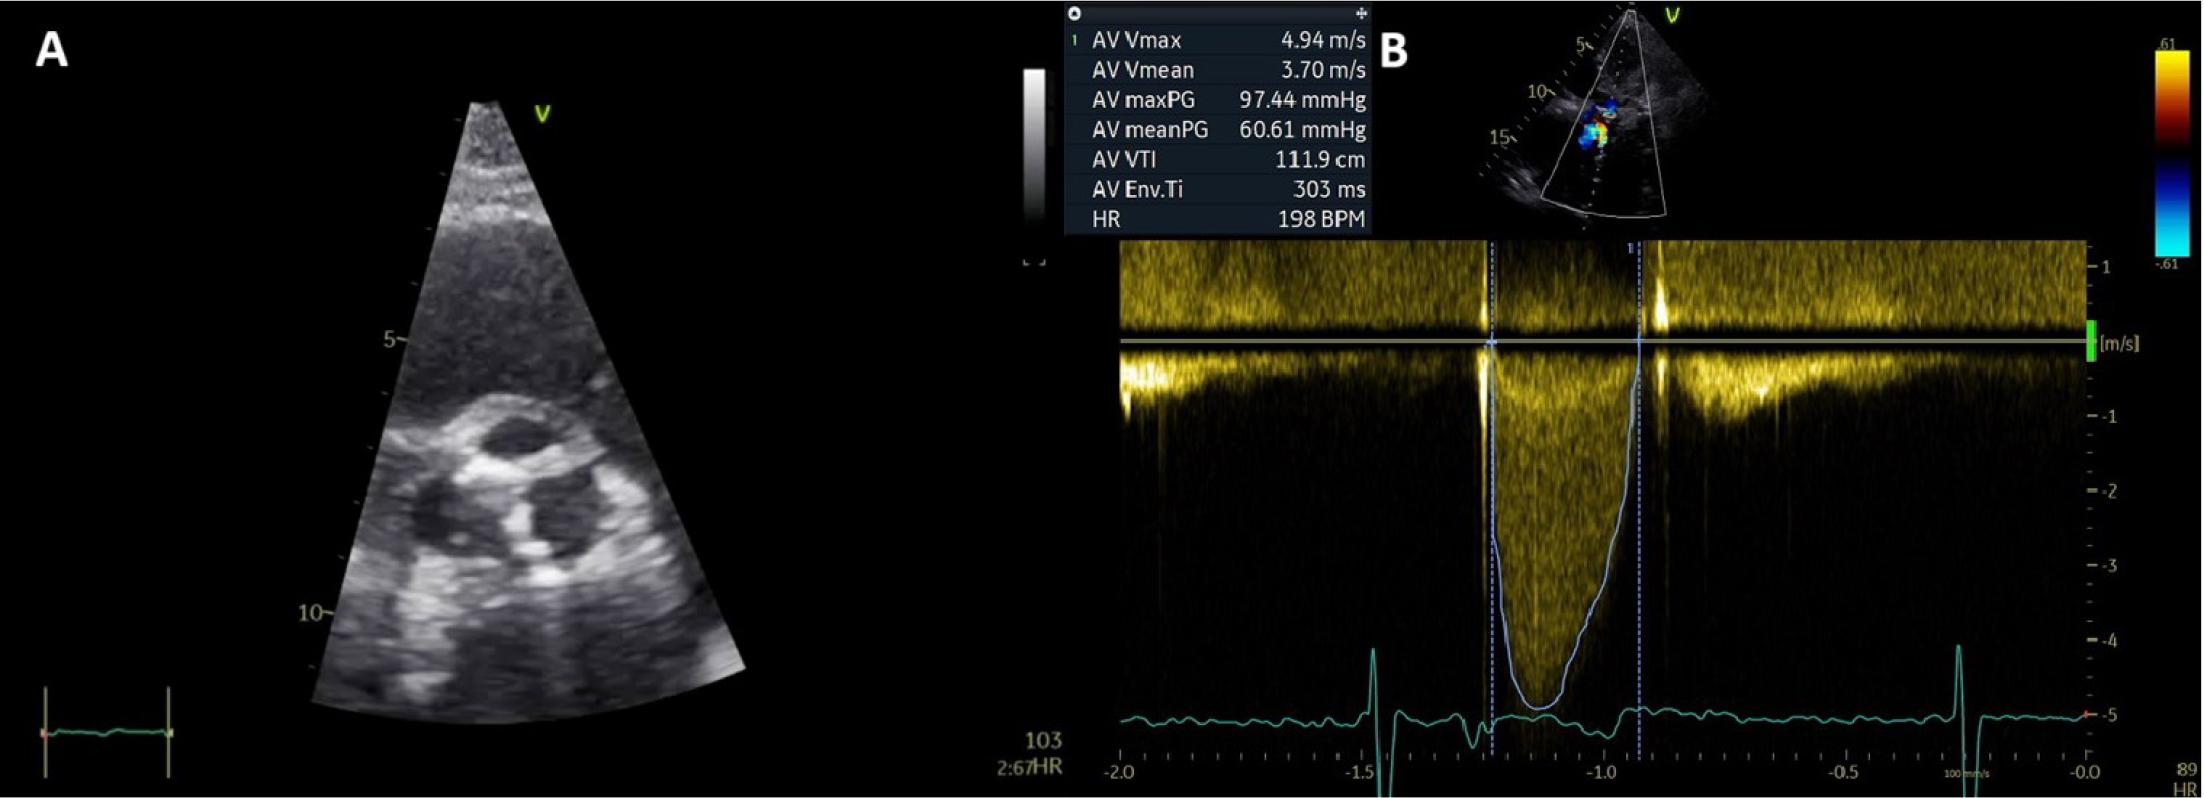

On current presentation, the patient was afebrile and hemodynamically stable, with signs of systemic congestion – jugular vein distention, liver enlargement and mild peripheral edema. Cardiac auscultation revealed a loud systolic murmur in the aortic area and the metallic sounds of mitral prosthesis in the mitral area. Laboratory tests showed a BNP of 466 pg/ml, an increased INR beyond the therapeutic range (4.3), mild anemia (Hb 10.2 g/dl) and mild renal dysfunction (creatinine 1.5 mg/dl), with no signs of an inflammatory syndrome. The electrocardiogram on admission indicated AFib with a ventricular-paced rhythm. Transthoracic echocardiography revealed a non-dilated left ventricle with preserved global systolic function, severe biatrial enlargement, a normally functioning mechanical mitral prosthesis and a severely dysfunctional (previously known) tricuspid mechanical prosthesis. The right ventricle was dilated, with mild systolic dysfunction, and an IVC of 20 mm was revealed, with <50% respiratory variation. Severe aortic stenosis (AS) was noted with significant progression of the valve lesion compared to previous evaluations (Figure 3).

Transthoracic echocardiography. A) 2D parasternal short axis view of the aortic valve showing severe valvular calcifications. B) CW Doppler interrogation showing high velocity transvalvular aortic flow.